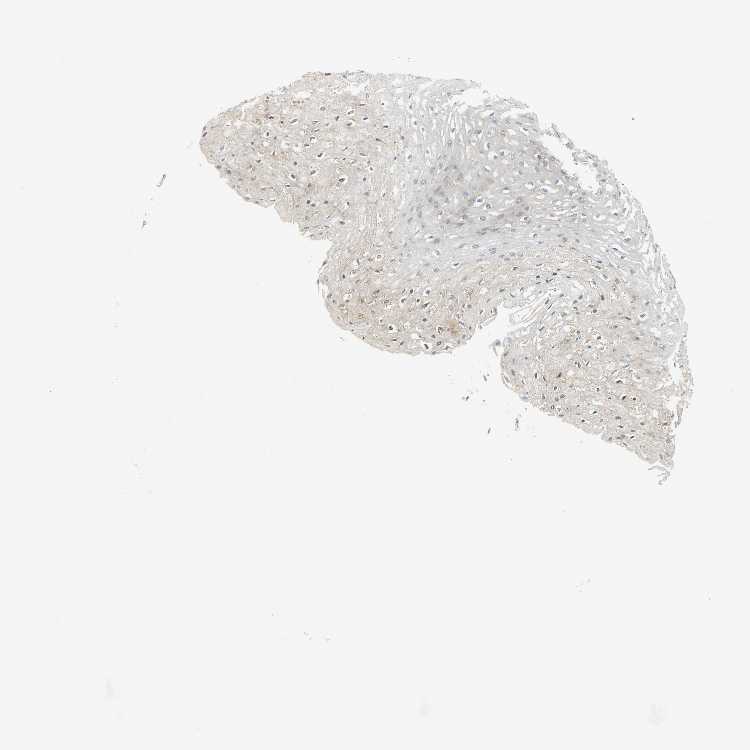

ESOPHAGUS - Antibody stainingi

Antibody staining in the annotated cell types in the current human tissue is reported as not detected, low, medium, or high, based on conventional immunohistochemistry profiling in selected tissues. This score is based on the combination of the staining intensity and fraction of stained cells.

Each image is clickable and will lead to virtual microscopy that enables deeper exploration of all samples and also displays staining intensity scores, fraction scores and subcellular localization as well as patient and tissue information for each sample.

Antibody HPA006136

Squamous epithelial cells Low